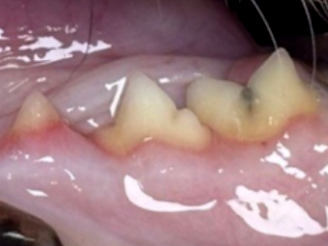

1. 부정교합

고양이도 품종에 따라 주둥이가 짧거나 긴 경우가 있습니다.

특히 단두종 고양이는 교합 이상이 잘 발생합니다.

어릴 때 적절한 검사와 치료를 통해

문제가 되는 치아를 발치하거나 관리하면

추가적인 통증과 손상을 줄일 수 있습니다.

2. 과잉치아

고양이는 결손치보다 과잉치아가 더 흔한 편입니다.

과잉치아를 방치할 경우 치석이 쉽게 쌓이고 염증이 발생해

주변 치아까지 손상될 수 있습니다.